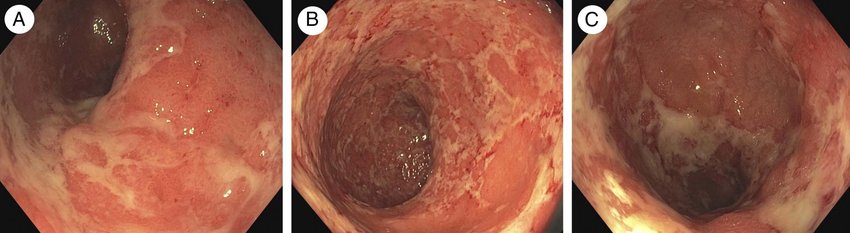

As part of your management plan, you organise a flexible sigmoidoscopy to get imaging of the patient’s large bowel. The images are below.

BONUS QUESTION: Based on the imaging findings, and given the likely diagnosis, what long-term treatment is indicated in this case?

This patient should be started on intravenous steroids (hydrocortisone) at a dose of 100mg QDS. Her care should be discussed with the gastroenterology team. She should also have a flexible sigmoidoscopy within 24 hours of presentation to visually assess the bowel and obtain biopsies to confirm the diagnosis histologically.

Answer to BONUS QUESTION

This patient should be commenced on 5-ASA treatment with Mesalazine. This can be administered orally, rectally (using suppositories or enemas) or both. In severe cases, patients might be escalated directly to immunosuppressive biologic therapies such as Infliximab (anti-TNF monoclonal antibody). Mercaptopurines such as Azathioprine can also be used in the long-term management of IBD.

Image 1: Tofacitinib-Associated Iatrogenic Kaposi Sarcoma in a Patient With Ulcerative Colitis – Scientific Figure on ResearchGate. Available from: https://www.researchgate.net/figure/Sigmoidoscopy-findings-of-active-ulcerative-colitis-show-marked-erythematous-mucosa-lack_fig1_356482846 [accessed 17 Jan, 2024]